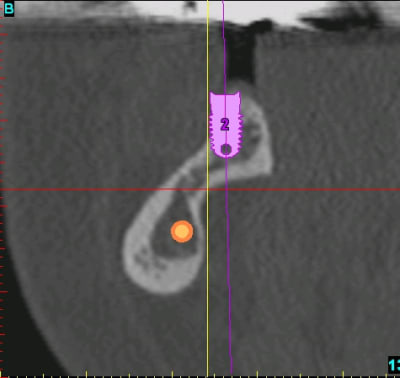

Pour se faire une meilleure idée de ton boulot, ce serait bien d'avoir qq coupes pour avoir une meilleure idée de l'objectif de cette ROG.

voilà pour compléter...

pano et les coupes pour les 2 futurs implants...

ce qui me posait problème, c'est l'inclinaison et la forme de la branche horizontale dans cette zone rendant l'implantation simultanée extrêmement délicate...pour ne pas dire risquée...

Comme quoi la pano veux rien dire ! La forme de la crête est môche !

Je renouvelle ma suggestion/ question : pourquoi pas 2 vis à émergence haute, inclinée d'env 30° par rapport à l'implant, et une plus basse entre les 2 précédents orthogonale à la surface osseuse ?

Mario, je ne sais pas si çà se voit bien sur la vidéo, mais les vis sont à peu près perpendiculaires à la corticale vestibulaire...donc, je pense que çà permet de préserver et le volume et la hauteur, non?

le principe c'est de se matérialiser mentalement la future crête et de disposer les vis de façon à ce qu'elles soient perpendiculaires à la future corticale et non pas perpendiculaires à la corticale déjà existante. C'est ce que l'on voit sur la coupe de clio et sur le schéma de mario.